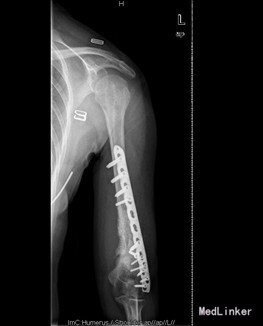

患者女,39岁,因“左肱骨骨折术后左肩关节左肘关节活动障碍6月”入院。 6月前患者外伤致左肱骨中下段粉碎性骨折,患者到当地人民医院行左肱骨骨折髓内钉及切开钢丝捆扎固定手术治疗(具体手术方式不详)。术后手术伤口恢复可,但患者左肩关节活动明显受限,并左肱骨下份肿胀严重,左肘关节活动稍受限。现患者左肩关节及左肘关节活动无明显好转,左上臂下段肿胀,皮温高。今患者到我院求进一步治疗。

查体:左上肢肱骨下段内侧有一10cm手术疤痕,下段肿胀,皮肤无明显发红。余四肢未见异常,活动无受限;左肱骨下份肿胀,未触及局限包块及波动感,肿胀区皮温高。桡动脉搏动正常。左肩关节活动明显受限,外展约20度,前伸后屈约20度,内外旋约15度,肘关节伸0度、屈45度。余关节活动无异常。 辅查:X片示左肱骨中下段骨折术后,内固定在位。

初步诊断:1、左肱骨骨折术后骨不愈合。2、左肩、左肘关节活动障碍 诊疗计划:择期行左肱骨髓内钉取出术、左肱骨骨折钢板螺钉内固定术,人工骨植骨。